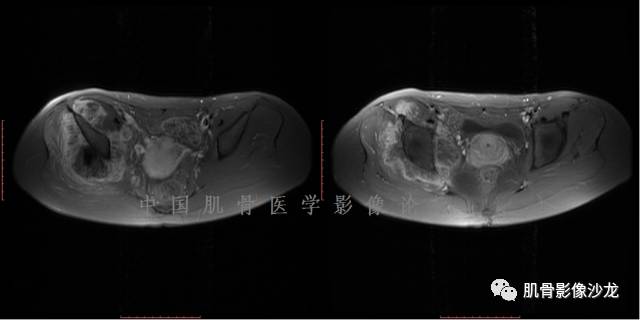

1、软骨肉瘤可以有膨胀性骨质破坏(病例3,4),可以有溶骨性骨质破坏(病例2),局部皮质因为破坏变薄,中断 ;

2、软骨基质T2WI高信号,软骨小叶分叶状,也就会出现高老师提到的骨内膜扇贝形压迹。一般认为骨内膜扇贝形压迹超过骨皮质厚度的2/3是软骨肉瘤在长管状骨的特征性表现。如上图。3、软组织肿块或肿胀;

4、 钙化,环形,弓形,边缘模糊 ;

5、增强后进行性延迟,不均匀分割状强化, 会强化的纤维间隔,软骨小叶不会强化,关于老师们说到的钙化,软骨肉瘤不一定会有钙化 。